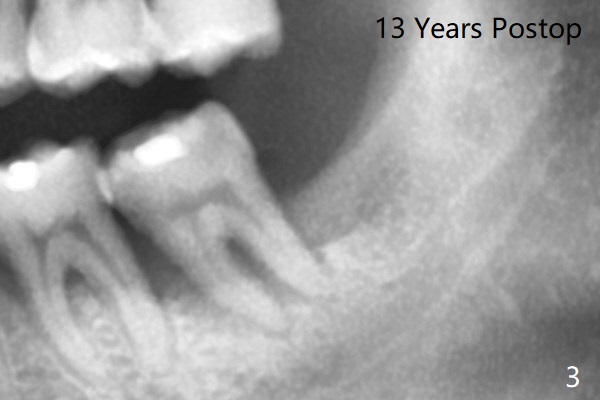

十三年后第二磨牙松动(图三),

磨牙间无骨     Last     Next